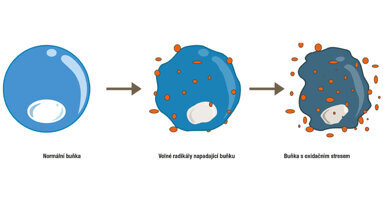

Výsledky studie ukázaly, že u starších lidí s periodontitidou je vyšší pravděpodobnost kalcifikace karotidy. „Je zřejmé, že u lidí s periodontitidou je větší pravděpodobnost vzniku kardiovaskulárních onemocnění a je u nich také zvýšené riziko úmrtí,“ řekla Wallin Bengtssonová.

Dále také zdůraznila důležitost zubních lékařů při pečlivé analýze všech pořízených panoramatických RTG snímků, protože zánět, který vzniká v souvislosti s periodontitidou může vést k ukládání tuku a plaku v různých tepnách těla.